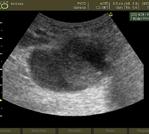

Fig.9. Pseudoanevrism aortic Fig.10. Anevrism aortic trombozat

Fig.11. Tromboză venă femurală dreaptă

• trombi, disecții prin examinarea arterelor și venelor mari pentru identificarea modificărilor de tip: anevrism aortic (fig.9) cu disecție, pseudoanevrism aortic (fig.10), efracție de perete cu hemoretroperitoneu; situații în care este necesară trimiterea rapidă spre un serviciu de chirurgie cardiovasculară și imagistică de tip computer tomograf, cu susținerea hemodinamică a pacientului;

• prezența trombozei venoase la nivel femural și popliteal (fig.11) ceea ce necesită investigarea semnelor de cord pulmonar acut și tratament anticoagulant sau trombolitic.